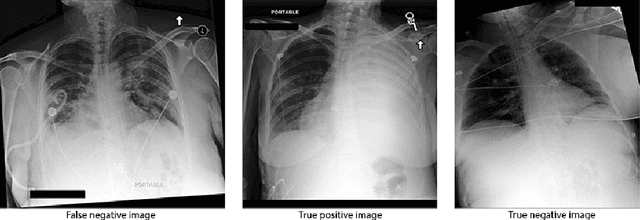

Abstract:Deep learning approaches applied to medical imaging have reached near-human or better-than-human performance on many diagnostic tasks. For instance, the CheXpert competition on detecting pathologies in chest x-rays has shown excellent multi-class classification performance. However, training and validating deep learning models require extensive collections of images and still produce false inferences, as identified by a human-in-the-loop. In this paper, we introduce a practical approach to improve the predictions of a pre-trained model through Few-Shot Learning (FSL). After training and validating a model, a small number of false inference images are collected to retrain the model using \textbf{\textit{Image Triplets}} - a false positive or false negative, a true positive, and a true negative. The retrained FSL model produces considerable gains in performance with only a few epochs and few images. In addition, FSL opens rapid retraining opportunities for human-in-the-loop systems, where a radiologist can relabel false inferences, and the model can be quickly retrained. We compare our retrained model performance with existing FSL approaches in medical imaging that train and evaluate models at once.